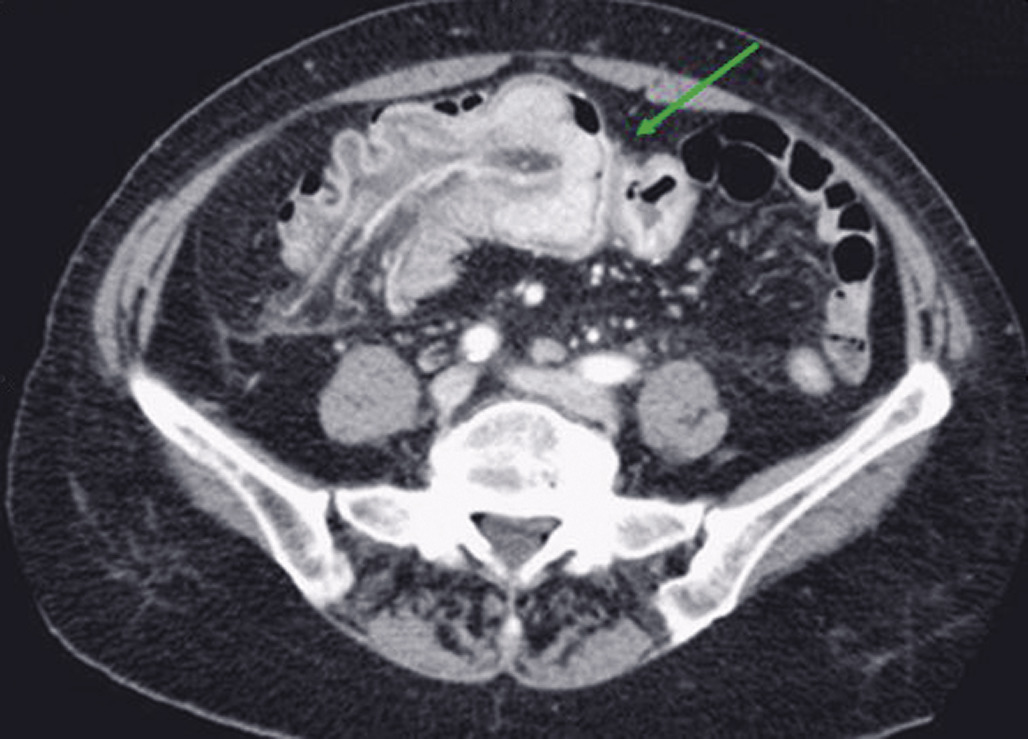

Les signes tomodensitométriques décelés sur le site de torsion sont classiquement (fig. 1 et 2) :

• anses dilatées, en forme de « U » ou de « C », à distribution radiaire ;

• présence de deux anses adjacentes collabées de forme ronde, ovale, triangulaire au niveau du site d’obstruction ;

• whirl sign, ou signe du tourbillon, qui correspond à l'enroulement des vaisseaux mésentériques et des mésos qui convergent vers le point de torsion mésentérique (fig. 1) ;

• le signe du bec, qui correspond à la visualisation, en coupe longitudinale, d’un aspect en pointe effilée reflétant à la diminution progressive du calibre intestinal jusqu'au niveau de l’obstruction (fig. 2).